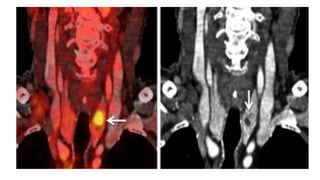

• Ectopic thyroid tissue

Ectopic?

A radioiodine stan shows the left thyroid lobe extending inferiorly in a substernal goiter.